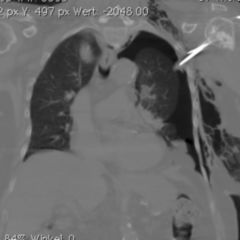

Die Folge dieses Verschlusses ist ein symptomloser Hydrokolpos mit Flüssigkeitsansammlung in der Vagina oder Hydrometrokolpos mit Flüssigkeitsansammlung auch im Uterus bei Neugeborenen. Diese Flüssigkeit besteht aus Sekret der mütterlicherseits hormonell stimulierten Vaginalschleimhaut.

Mit der Menarche, dem ersten Auftreten der Regelblutung in der Pubertät tritt ein Hämatokolpos mit Aufstau von Menstruationsblut in der Vagina oder eine Hämatometra (Hämatokolpos) mit Aufstau auch in den Uterus hinein auf. Die Öffnung des Hymens erfolgt in diesen Fällen operativ.